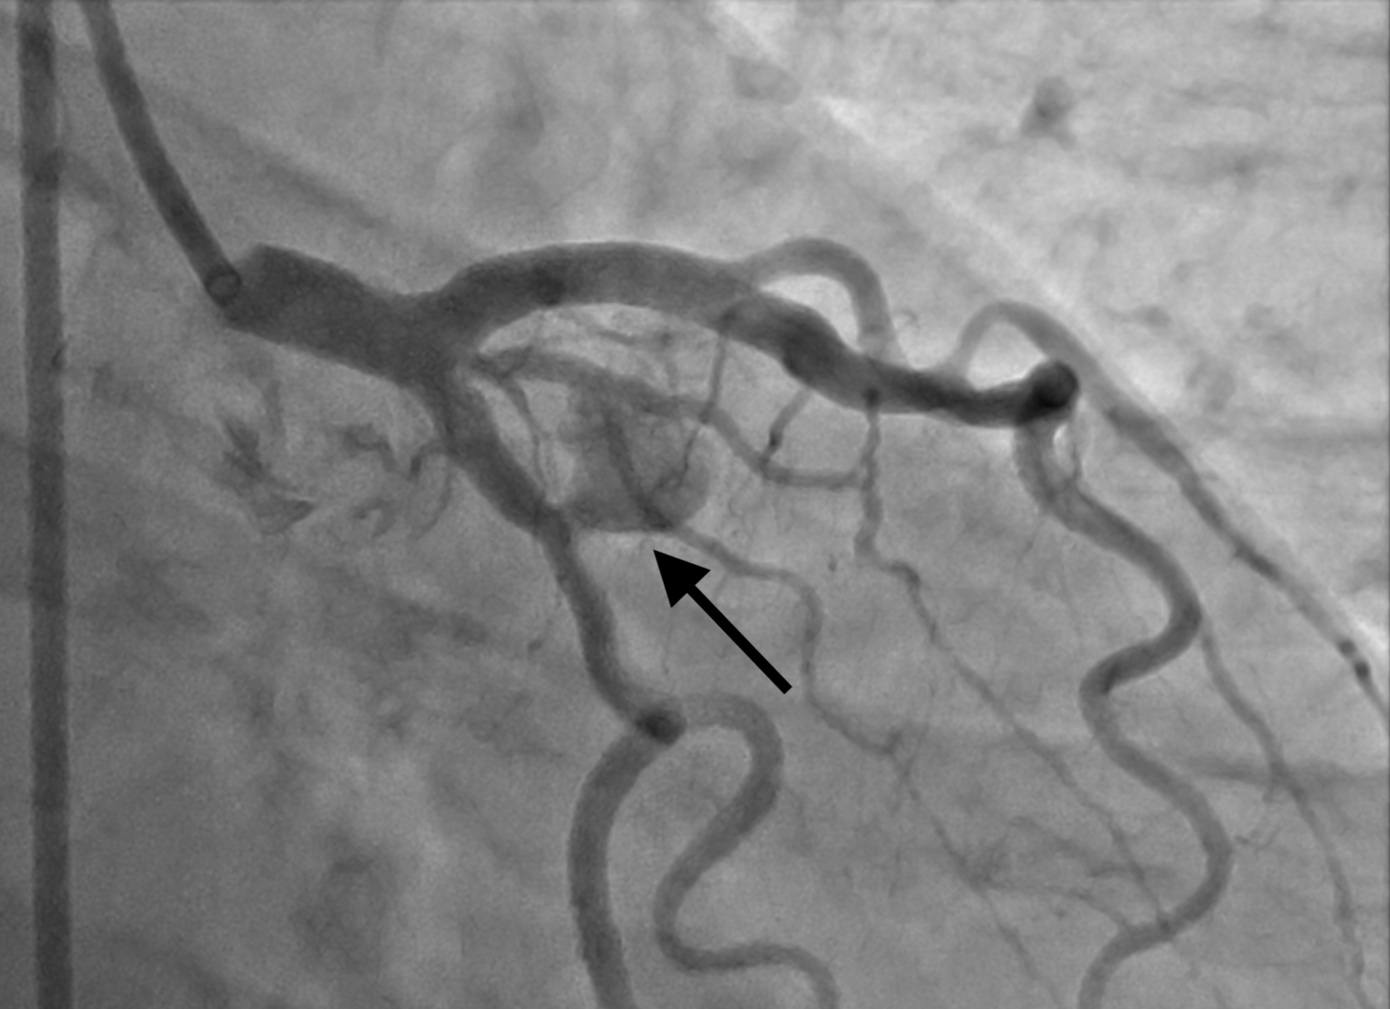

| Túi giả phình (vị trí đầu mũi tên) trên hình ảnh kiểm tra cho người bệnh trước khi can thiệp |

Người bệnh được chỉ định thực hiện các kiểm tra chuyên sâu truy tìm bệnh lý bằng phương pháp chụp, can thiệp động mạch vành dưới sự hỗ trợ của hệ thống chụp mạch số hoá (DSA). BS Tấn Việt cho biết, kết quả kiểm tra ghi nhận, bệnh nhân bị hẹp 30% nhánh chéo D1 và có túi giả phình động mạch vành (kích thước 7.6 x 11.6mm). Đây là bệnh lý hiếm gặp, có nguy cơ vỡ túi giả phình, gây tràn máu màng ngoài tim khiến người bệnh nhanh chóng tử vong.